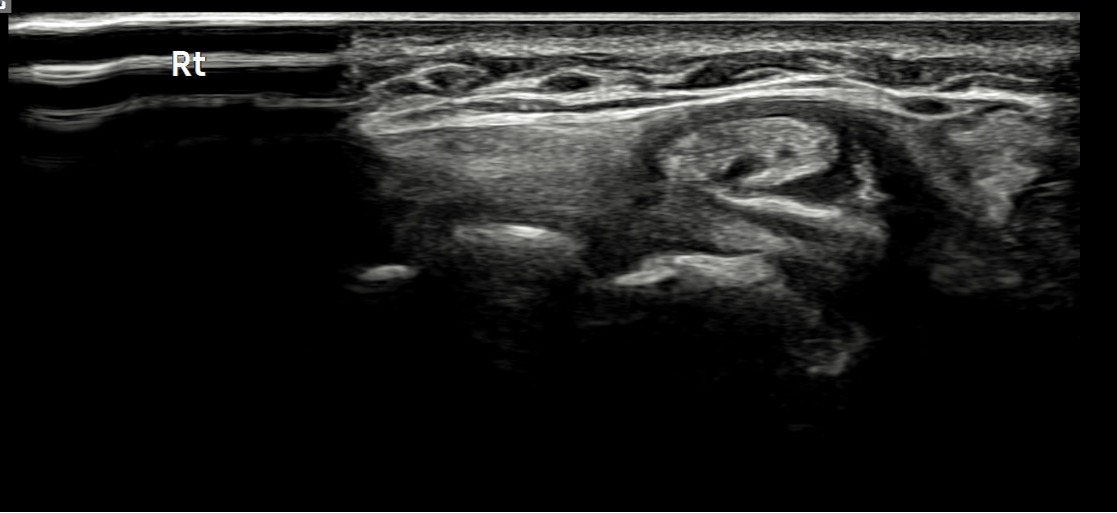

치료 후기에 사용된 전/후 검사 사진은 동일 인물의 결과이며 각 지점 동일 조건에서 촬영되었습니다.

개인에 따라 치료 결과에 차이가 있을 수 있으며, 부작용이 발생할 수 있습니다. 내원 후 충분한 상담을 받으시고 치료를 진행하시면 됩니다.

- 치료기간 : 25 . 4 . 25 ~ 25 . 6 . 25

- 치료횟수 : 1Cycle(5 회)